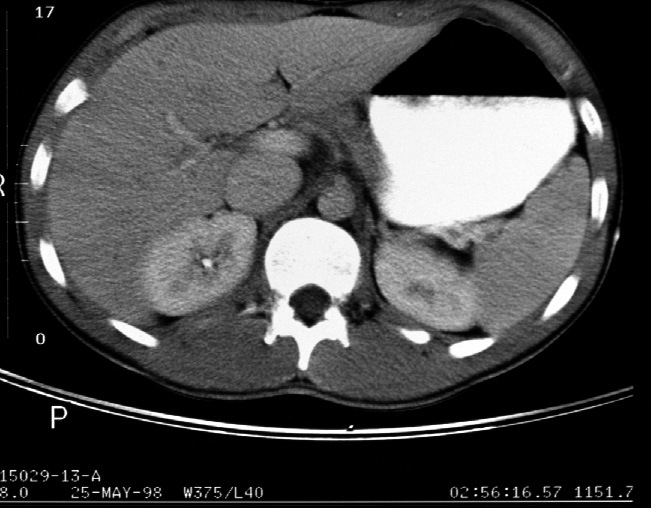

Identify -- stomach, liver, right kidney, left kidney, aorta, inferior

vena cava, diaphragmatic crura, hepatic artery, portal vein, spleen